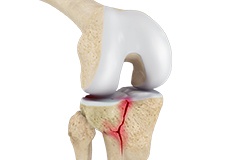

Knee Fracture

A fracture is a condition in which there is a break in the continuity of the bone. In younger individuals, these fractures are caused by high energy injuries, as from a motor vehicle accident. In older people, the most common cause is a weak and fragile bone.